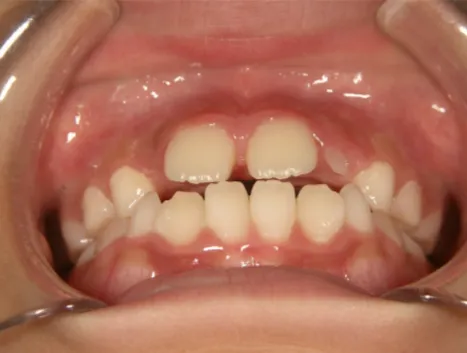

治療中➁小3:9y8m QH、BH、前歯並び替え終了

モノブロック装置(筋機能的咬合誘導装置)スタート